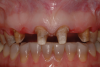

A patient presented with two defective 3-unit fixed partial dentures spanning teeth Nos. 6 through 8 and teeth Nos. 9 through 11 (Figure 7). The defective fixed partial dentures were removed (Figure 8), an impression was made, and traditional provisional fixed partial dentures without ovate pontics were placed. After the impression was sent to the laboratory, the lab technician prepared ovate pontic sites on the stone cast (Figure 9) and fabricated the new definitive bridges. On the day of insertion, the provisional fixed partial dentures were removed (Figure 10), ovate pontic sites were prepared using a teardrop-shaped diamond bur (Figure 11), and the sites were sounded to confirm that there was at least 2 mm from the base of the pontic site to the alveolar bone (Figure 12). The fixed partial dentures were cemented, and the postoperative healing was uneventful (Figure 13).